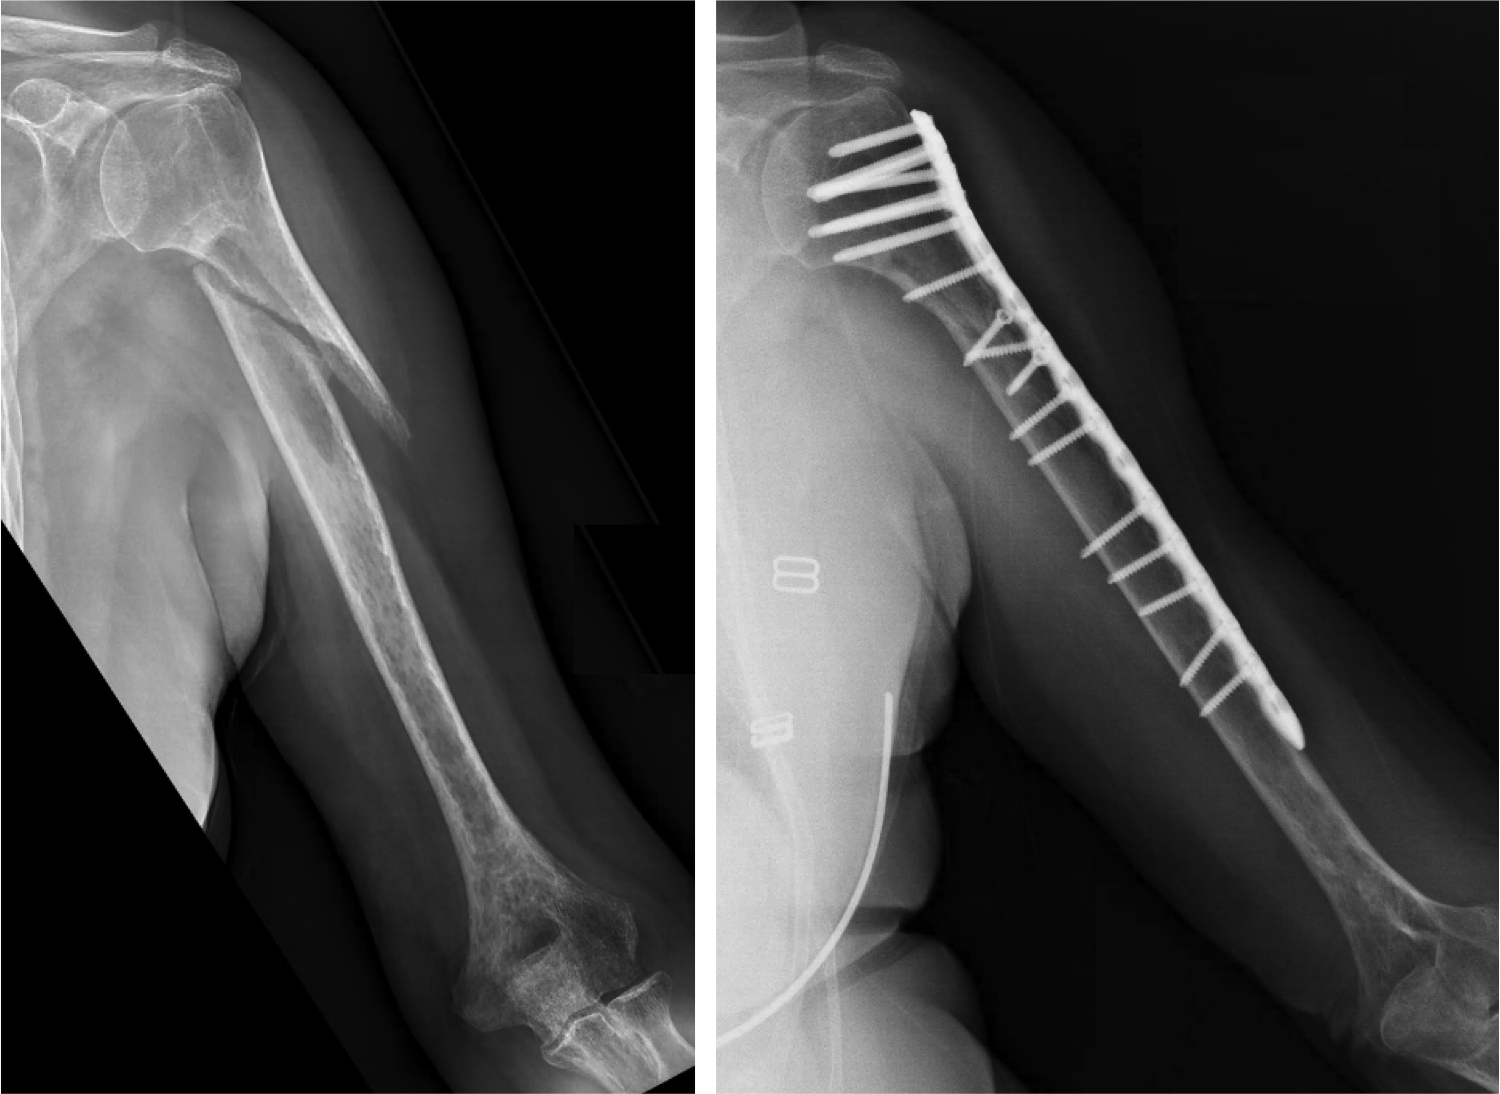

کی میتوانم مرخص شوم و چه مراقبتیهایی در طول بستری باید رعایت کنم؟ ترخیص شما بسته به زمان عمل جراحی و نوع شکستگی بین دو تا هفت روز بعد از...

کی میتوانم مرخص شوم و چه مراقبتیهایی در طول بستری باید رعایت کنم؟ ترخیص شما بسته به زمان عمل جراحی و نوع شکستگی بین دو تا هفت روز بعد از...